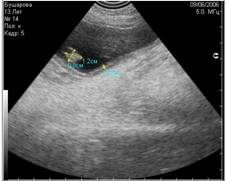

Рис. 8. На снимке представлен гиперэхогенный объект в полости мочевого пузыря, испускающий эхоакустическую тень. На основании этого артефакта, мы можем предположить, что этот объект является конкрементом. |

Рис. 9. На снимке представлен похожий по величине и эхогенности объект в полости мочевого пузыря, не испускающий эхоакустической тени. На основании этого признака, мы можем предположить, что изучаемый объект является новообразованием. |